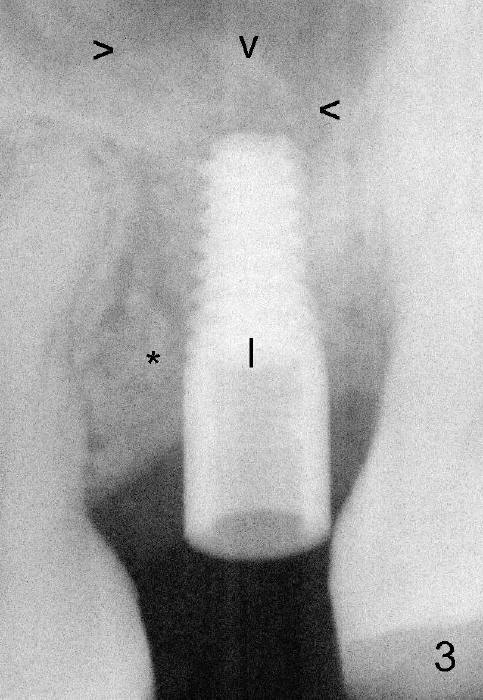

Exam immediately prior to surgery shows that the edentulous ridge is wide buccolingually. The mesiodistal space is less than 6 mm. It appears that a 4 mm implant is appropriate. Two piece implant is chosen over a one-piece one, because of large surface area of the former. After local anesthesia, a 3.5 mm tissue punch is used for access to the bone. A 1.5 mm pilot drill initiates osteotomy 8 mm in length (Fig.1 D). The drill is more or less in the middle of the edentulous space and 1 mm coronal to the sinus floor (^). Then a 2 mm pilot drill, 2.5 mm and 3 mm reamers are used to enlarge osteotomy (8 mm deep). Mixture of autogenous bone and Osteogen and 2.5 mm Bicon osteotome are used for sinus lift. The osteotome does not reach the intended depth of 10 mm. The osteotomy is extended with the 2 mm drill and 2.5 mm reamer (Fig.2 R) to barely perforate the sinus floor. When a 4x11 mm implant is being placed, it tends to deviate distally. The implant is backed up twice: initially it appears to lean mesially, but as it is seated deeper, it is deviated distally again (Fig.3). An immediate provisional has to be fabricated to prevent the space from further narrowing. A 3.5x3 mm abutment is placed. The mesial surface of the tooth #14 (Fig.4 black area) is trimmed for restoration. Why is the implant deviated? How to fix it?